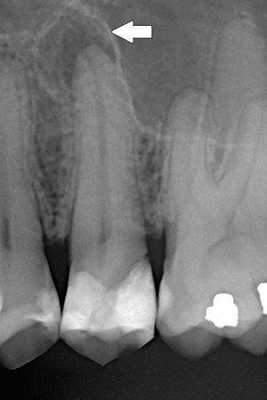

Диагностика периодонтита проводится на основании жалоб пациента, анамнеза заболевания, оценки общесоматического статуса, осмотра головы и шеи, полости рта, зуба, его перкуссии, зондирования и термопробы, электроодонтодиагностики (ЭОМ) и рентгенологического исследования. [10]

ЭОМ — это метод стоматологического исследования, основанный на определении порогового возбуждения болевых и тактильных рецепторов пульпы зуба при прохождении через неё электрического тока.

Окончательно диагноз хронического периодонтита устанавливается на основании данных радиовизиографии и электроодонтодиагностики. В некоторых клинических ситуациях может быть показана фистулография. В большинстве случаев распознавание хронического периодонтита возможно только с учетом интерпретации рентгеновского снимка зуба, где определяется разрежение костной ткани (иногда деструкция твердых тканей корня зуба) в области апекса. Пороговое значение электровозбудимости пульпы при хроническом периодонтите превышает 100 мкА.

- Рентгенография зуба. В случае хронического гранулирующего периодонтита в апикальной области обнаруживается участок разрежения костной ткани с нечеткими границами размерами от 1 до 8 мм. Хронический гранулематозный периодонтит характеризуется ясно очерченными округлыми контурами области разрушения костной структуры вокруг верхушки корня зуба. Хронический фиброзный периодонтит на рентгенограмме проявляет себя расширенным периодонтальным пространством в апикальной области при отсутствии резорбции костной стенки альвеолы.